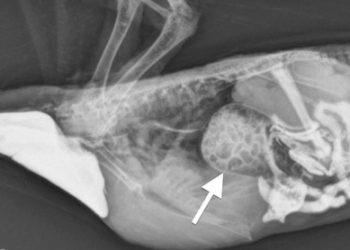

Read moreDetailsEvcil Kuşların Proventriküler Dilatasyon hastalığı. Bu hastalığa Kuşlarda Bornovirus hastalığı olarak da adlandırılmatadır. Daha önceleri Proventriküler Dilatasyon hastalığın etiyolojisi bilinmiyordu....